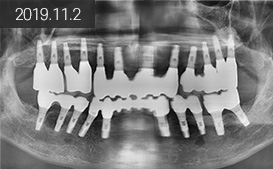

“ 지방에서 소개로 내원,

흔들리는 치아 발치 후

치조골 이식을 동반한 15개 임플란트 식립 후

19개 치아 복원 ”